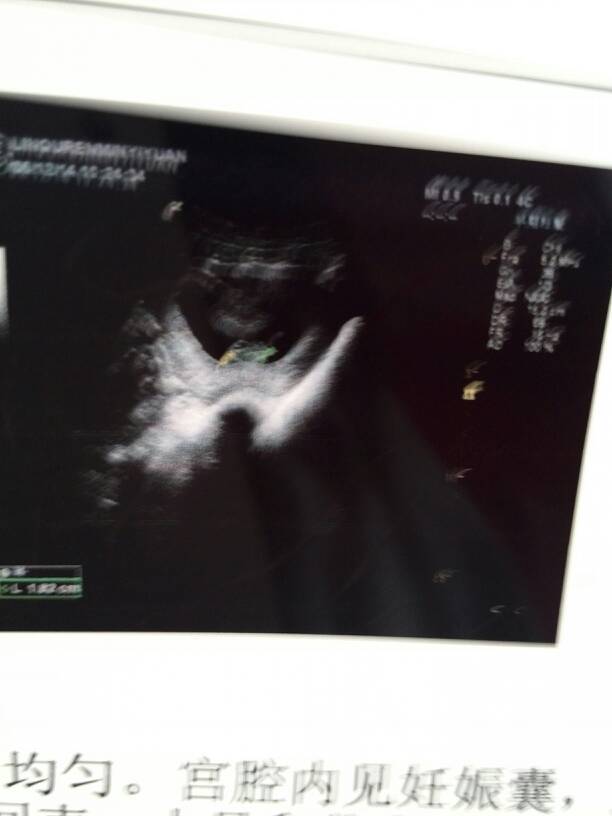

两个月的彩超,有懂的宝妈帮忙看看男宝还是女宝 两个月的彩超,有懂的宝妈帮忙看看男宝还是女宝 点击展开 ℡祐掱畵情 2014-06-13 07:38 为您推荐: 其他回答 根据孕囊的状态, 大小,等判断不了胎儿的性别。需要在怀孕的十六周后,通过B超检查,确定胎儿的生殖器判断的,但是医院进行性别不合法的。 shenglongxiao 2014-06-13 07:39 相关问题 各位宝妈们帮看看四维彩超男宝女宝 三维彩超,宝妈们医生们帮忙看看,正常吗?羊水会少吗?胎儿会偏小吗?六个月了